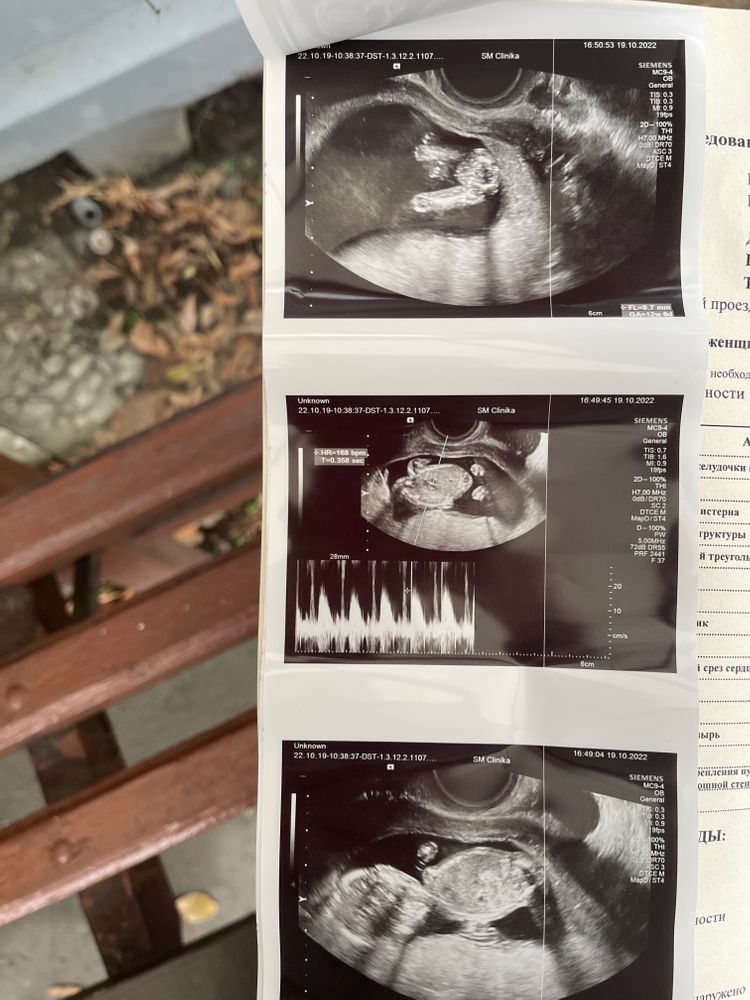

Валерия, считаете что у меня 100% мальчик ? Как и куда смотреть 🤣🙏

Polina Dyakova, вот, на фото, где вид снизу на область попы и бедер

Валерия, а какой срок? Если есть недель 15 хотя бы - это предположение имеет смысл, если меньше - то нет

Polina Dyakova, тогда с Вас взяли деньги ни за что, извините. На этом сроке у плода любого пола будет половой бугорок, который напоминает мужские гениталии. Только у девочек он потом модифицируется в клитор,а у мальчиков в пенис. Пол на сроке до 15 недель судят по углу наклона полового бугорка и это имеет высокую вероятность ошибки. Судя по ракурсу УЗИ узист этого не знал и смотреть по "классическому" ракурсу снизу бедер, что актуально для более поздних сроков.

Polina Dyakova, пипирку маленькую вижу) раз что-то торчит - мальчик, у девочек там всё гладко, если срок больше 15 недель)

Чашка утреннего кофе, узист скзаала что из этой штучки либо растёт мужское добро, либо останется как есть и станет клит*ром

Polina Dyakova, я думала больше) рано вы пошли пол определять) если хотите точно - это не раньше 15-16 недель. В 13 могут предположить, и на хорошем аппарате у опытного узиста часто не ошибаются, но, тем не менее, на таком сроке ошибка с полом ещё возможна.

Сделайте анализ крови, там вероятность определения пола 99,9%, если так важно. Мы в 11+1 делали, потому что оба любопытные, да и на узи очень часто не точно или ошибаются

Так видно же, что мальчик)